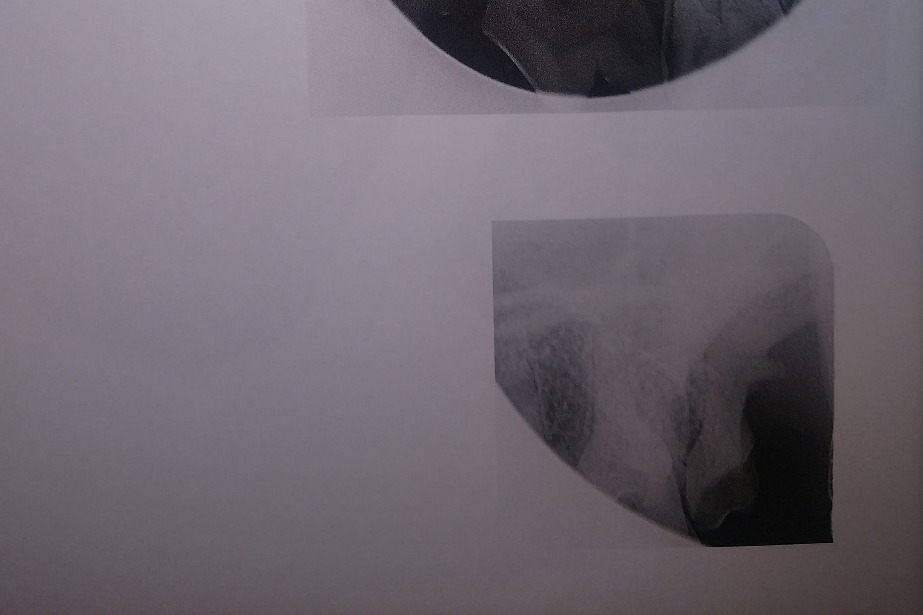

The following photos are her radiographs for anyone that knows how to read them, so you can see all the dead teeth that need future extractions, and some show the root canals:

The radiographs laid out a dim story of that long term damage: all 4 canine teeth were dead, 2 of those canines were broken off from the recent attempt on the gate; all of her lower incisors, and several molars on each side were also dead. The vet was surprised, in spite of massively evident wear and tear, that her upper incisors appeared to still be alive. More of her teeth were dead than live. However, there was some good news in that her gums were completely free of gum disease, she had very little plaque and tartar buildup, and that she hadn't lost any of the bone her teeth were seated in.

In the future, she will need at least one additional root canal on her other bottom canine, and either a root canal or an extraction on the other upper canine. She will also need all the rest of the dead teeth in her mouth extracted. I expect the remaining work to amount to a minimum of $4,000.